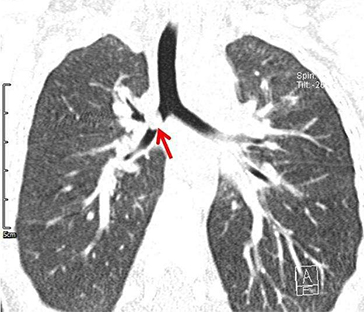

近日,山东省立医院东院耳鼻喉科门诊接诊了一例气管异物患儿。中午时分,一对焦急的夫妇来到耳鼻喉门诊,手中抱着1岁的患儿,着急的同医生说:孩子在家吃炒豆呛着了,老咳嗽。医生详细询问病情、查体听诊后,考虑气管异物。于是值班医生紧急安排肺部CT检查,发现右肺叶有异物堵塞。医生告诉患儿家长,为保证患儿生命安全,需要尽快安排手术取出异物。在东院耳鼻喉科医生的努力下,迅速联系到手术室,紧急安排了急症手术,通过支气管内镜取出了患儿右肺主支气管的异物。经确认,异物为炒熟的豆皮和豆粒。通过我科医生,手术麻醉科医生和护士的齐心合力,以最快的时间抢救了患儿生命,避免了悲剧的发生!